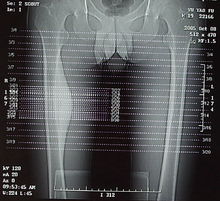

大腿的X光片1、人下肢從臀部到膝蓋的一段,也叫股。